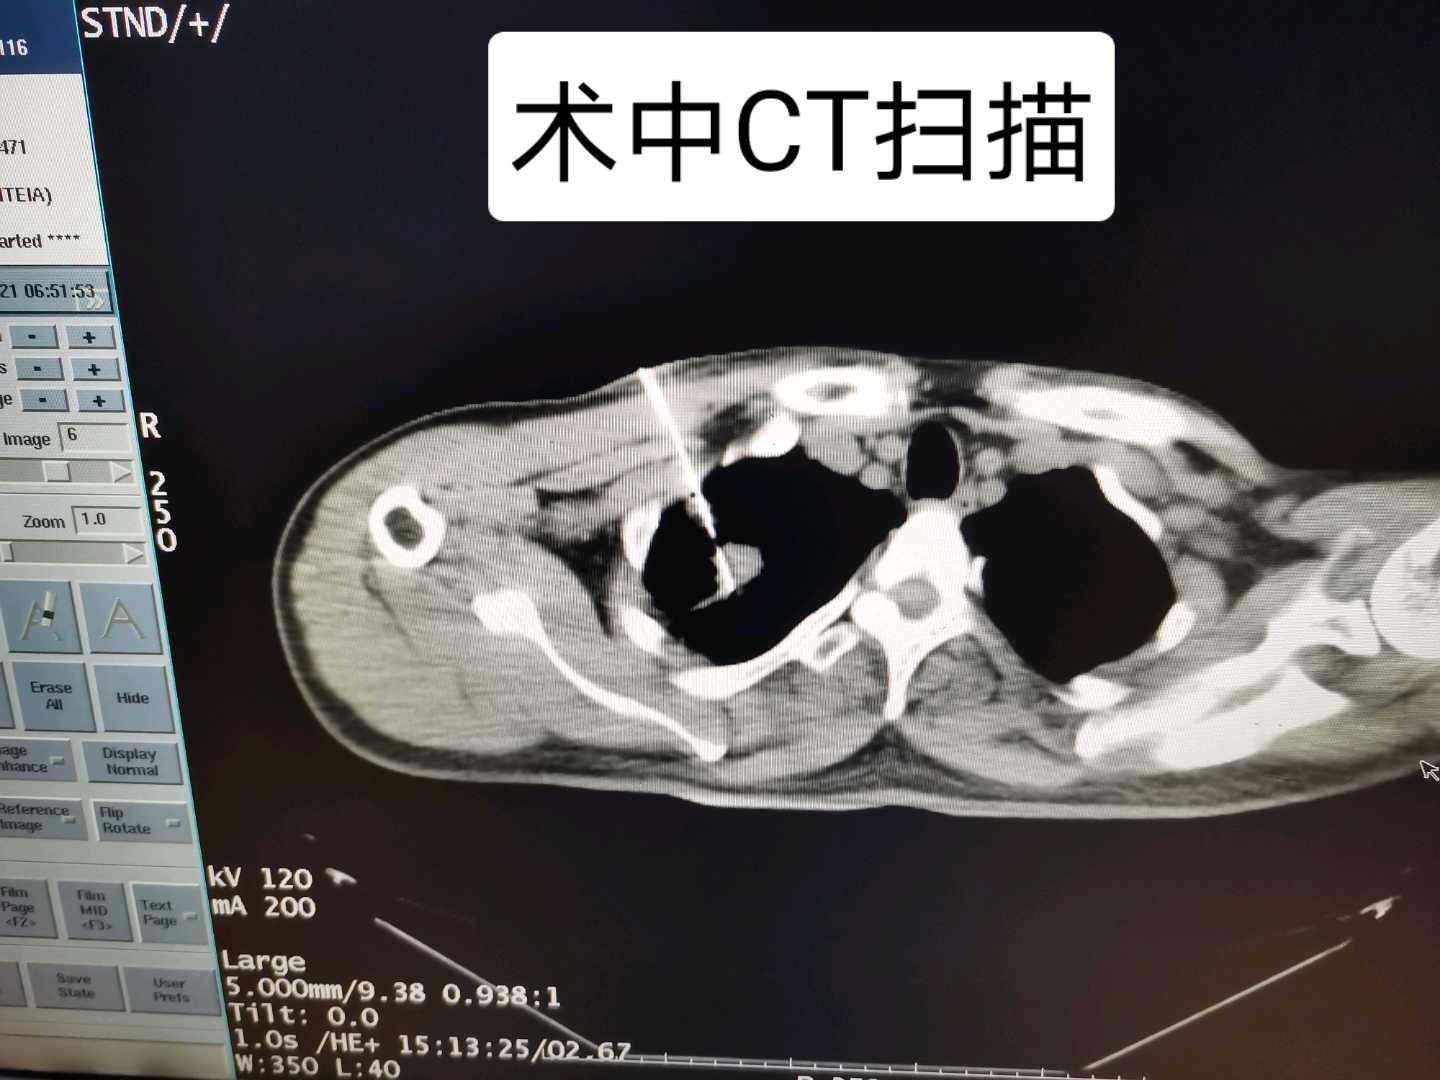

我是河北燕达医院肿瘤科主治医师刘亚宁,跟大家分享一例肺占位穿刺活检,介绍一下肿瘤穿刺活检检查。下面这是肺肿瘤肿瘤穿刺活检的过程,右肺二公分占位,通过CT引导下穿刺活检来明确肿瘤病理类型。操作很顺利,病人恢复好,无气胸发生,病理类型明确为肺腺癌。 EGFR基因检测提示19外显子突变由于患者活检前PETCT提示右肺占位,多发骨破坏,符合小病灶大转移特点,临床分期IV期,目前口服阿法替尼治疗。后续会有跟进随访疗效。

术前CT检查